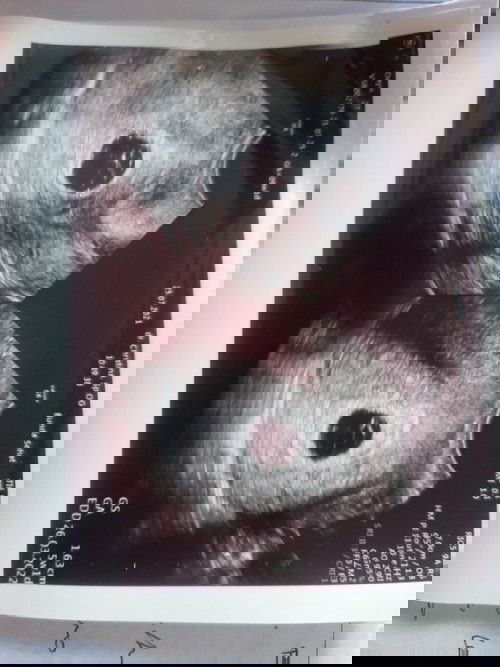

Terimakasih nak sudah berjuang selama 8 minggu 🤗

Terimakasih nak, kamu sudah pernah hadir dirahim mama. Walau hanya sebentar. Insyallah mama iklas. Terimakasih sayang. Doakan mama sama papa dari surga agar secepatnya bisa diberikan adik kamu ya nak.